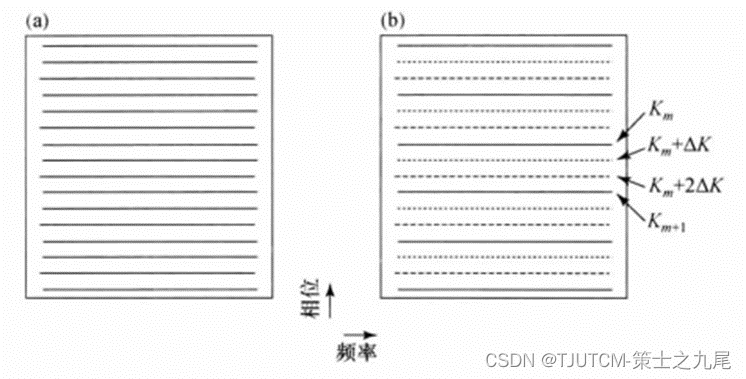

(a)图为全采样空间。

(b)加速因子R=3并行成像K空间,虚线代表没有采的K空间行,两个测量的行Km和Km+1之间缺失的两行分别是Km+ΔK,Km+2ΔK(ΔK是奈奎斯特取样定理要求的相位编码步距)。

在笛卡尔采集中扫描时间正比于相位编码步数。利用多线圈以欠采样方式同时采集数据,从而节省了时间,提高了扫描速度。增大K空间行的间距R倍,而保持覆盖的最大K空间范围(空间分辨率)不变,则扫描时间将降低R倍,于是 在并行成像中R被称为“加速因子”或(扫描时间的)“降低因子” 。

增大相位编码行的间距会导致FOV减小,如果物体延申到缩小的FOV外面,就会发生混叠或卷绕伪影。